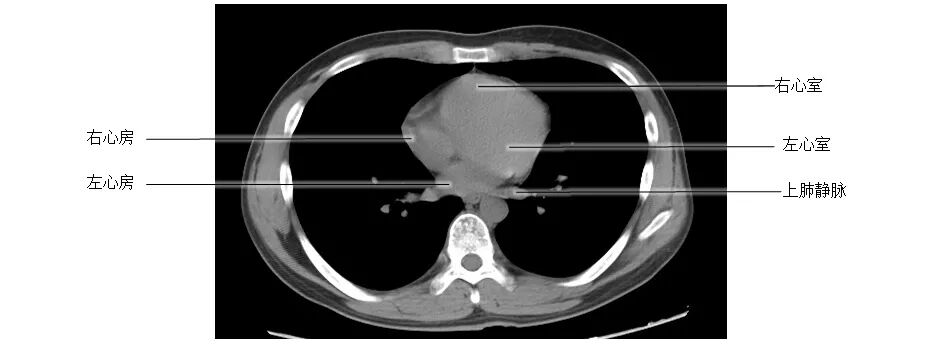

正常胸部CT影像是从横断面显示解剖和病变,可显示的结构包括胸廓、气管和支气管、肺、胸膜、纵隔和膈,CT的重建图像可从各个角度显示胸部解剖情况。不论采用何种图像显示方式,把握基本解剖结构都是必不可少的,一起学习胸部CT肺窗和纵隔窗的正常解剖。

胸部CT纵膈窗